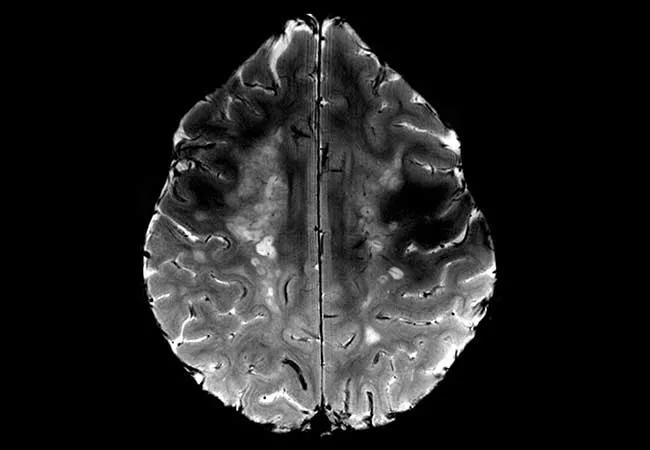

Another example is provided by the images below, which show the white matter in a patient with advanced MS. The lower-field (1.5T) image at the bottom shows a uniform field of signal hyperintensity (brightness), but the 7T image at the top allows details within the disease to be appreciated with greater resolution. Note the myriad rounded lesions that appear superimposed at 7T but appear coalesced at lower field.

MRIs of white matter in a patient with advanced MS taken at 7T (top) and at 1.5T (bottom).

Moreover, 7T reveals a central black dot at the center of nearly all lesions (arrow in the upper image shows one example), which represents the effects of blood flow in a central vein. This association is well established from microscopic pathology, and it can now be demonstrated on MRI with the advent of 7T. In the future, observation of this feature may help determine an MS diagnosis by distinguishing it from numerous look-alikes at lower magnetic field.